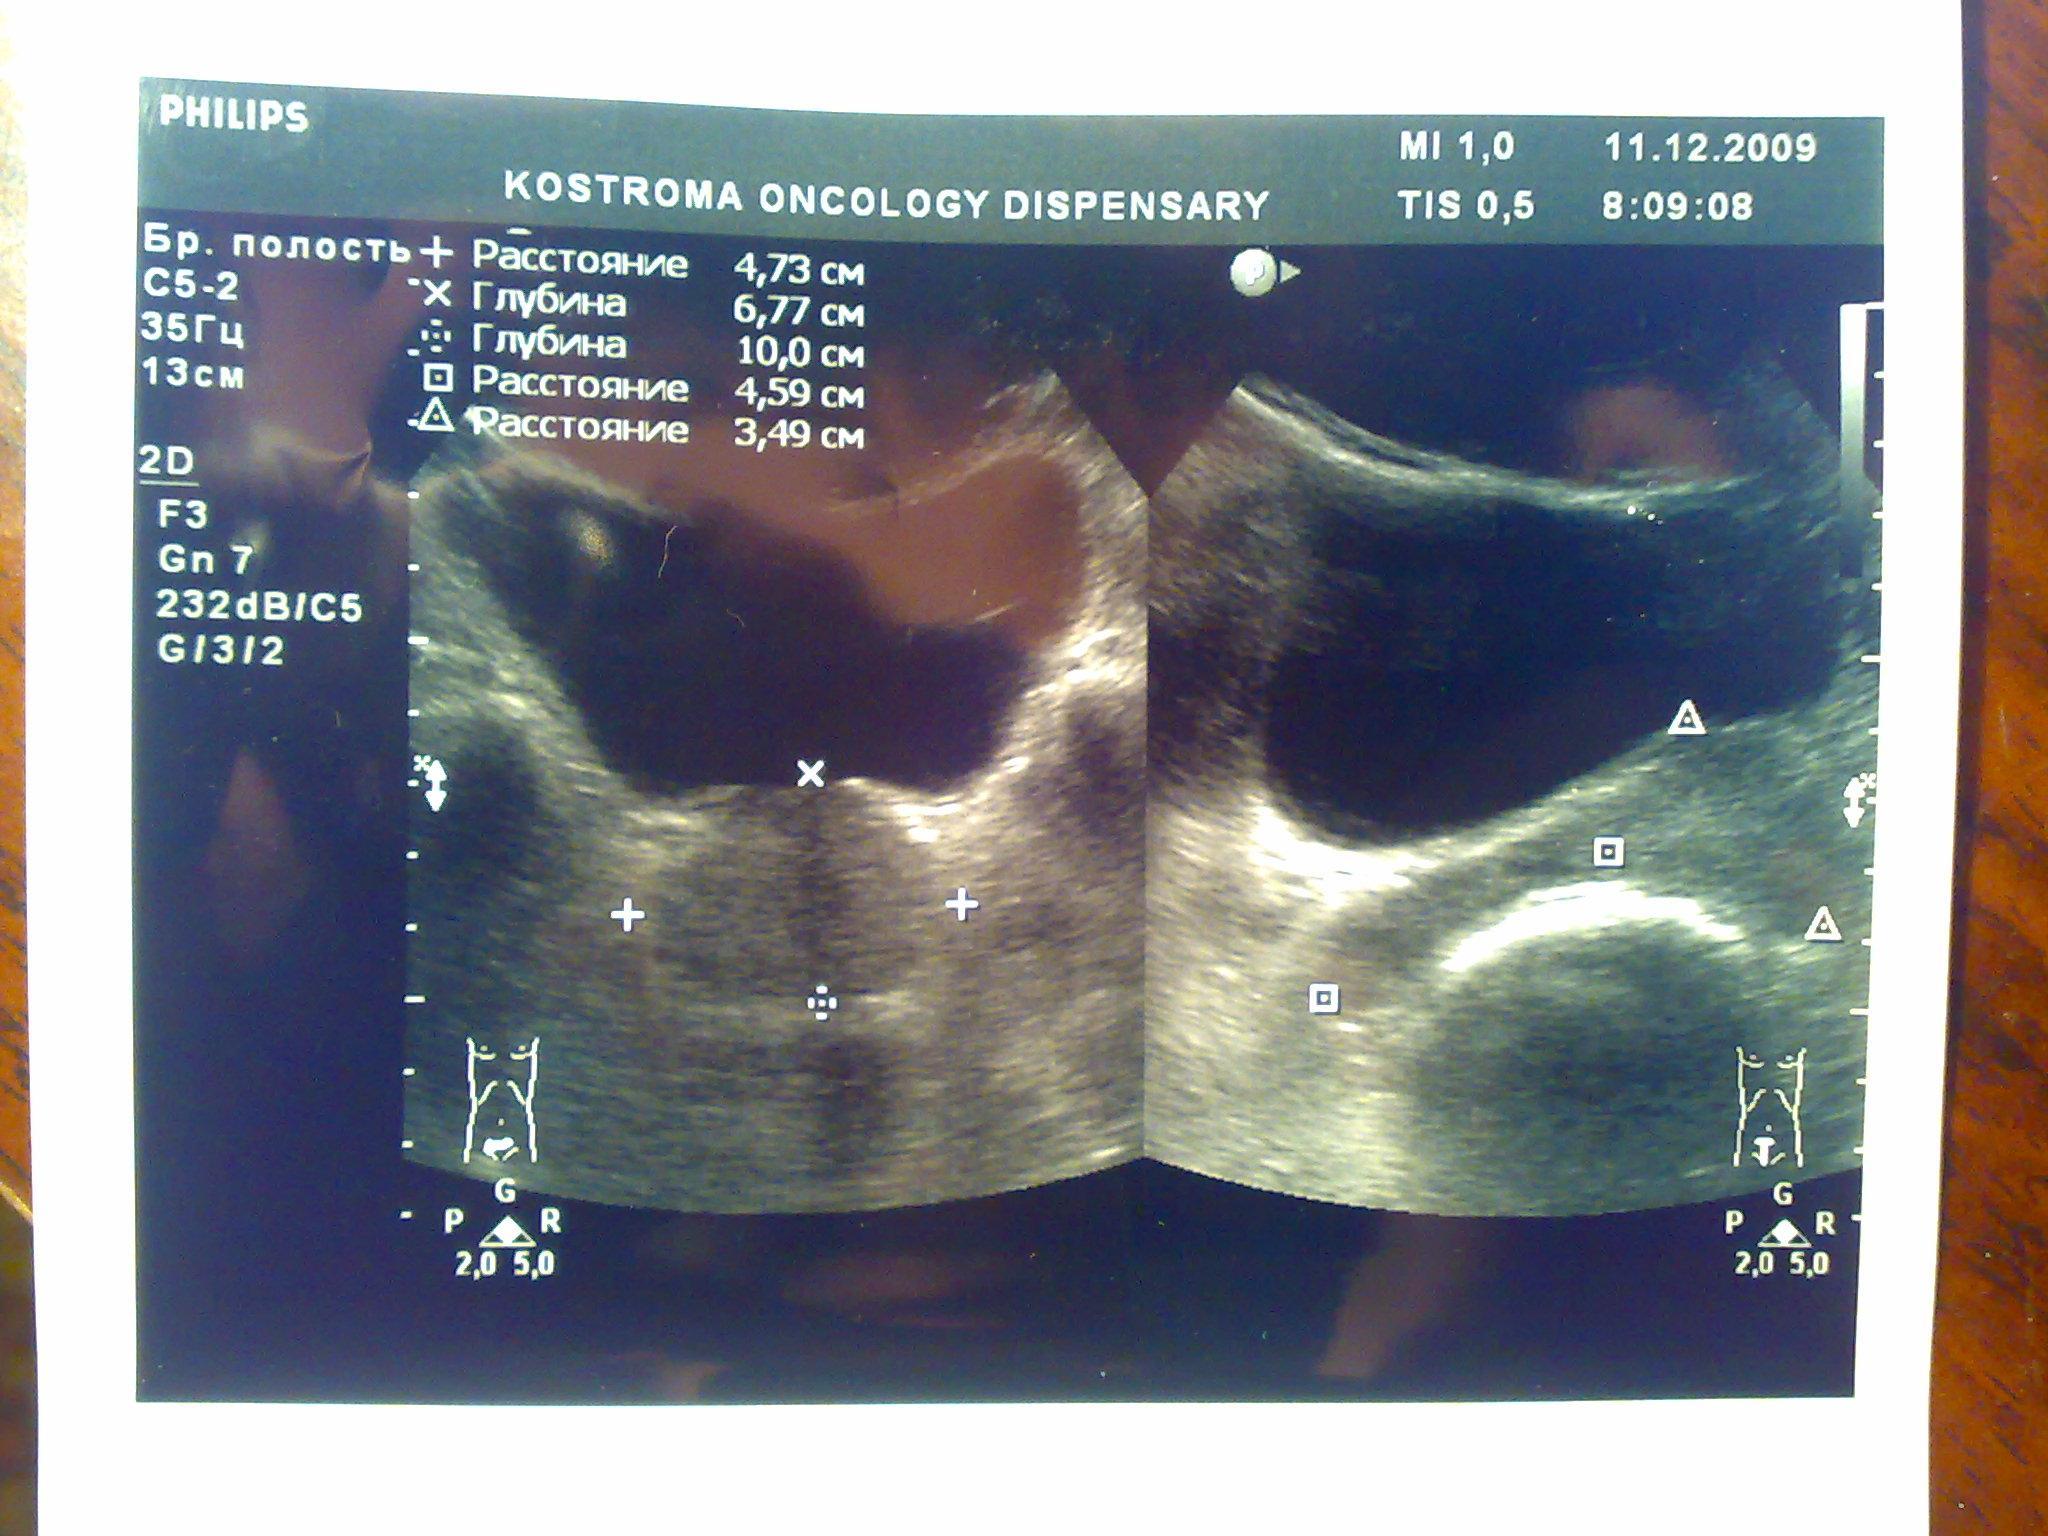

Посмотрите пожалуйста снимки узи, какие выводы можно сделать кроме увелечинных размеров? Может ли это влиять на эректильную функцию или изменение гормонального статуса? Болевых ощущений нет, есть небольшой дискомфорт, мочеиспускание в норме, но струя послабже чем была.Очень переживаю, ночами не сплю из-за нервов, без седативных уже и не уснуть.Заранее благодарен.

Ваши симтомы не связаны с предстательной железой. Вам нужен хороший психолог или психоаналитик. Уролог не нужен.